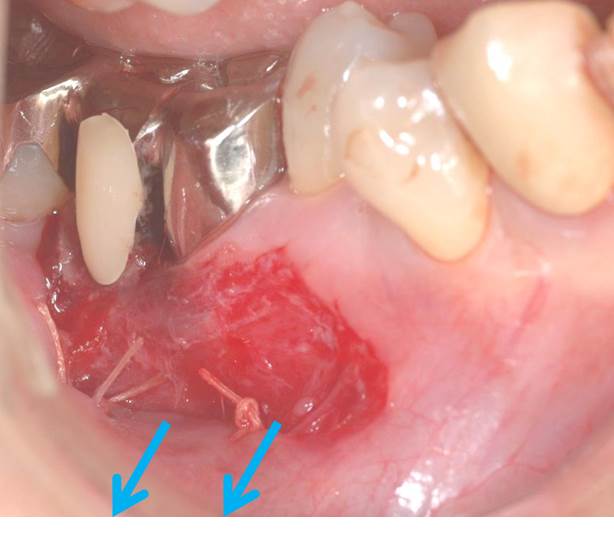

青の矢印は動く歯茎が歯の周りまで伸びてきているために、患者さんのブラッシングを邪魔します。

そこで、歯周外科処置によって、動く歯茎を下方向に移動しました。